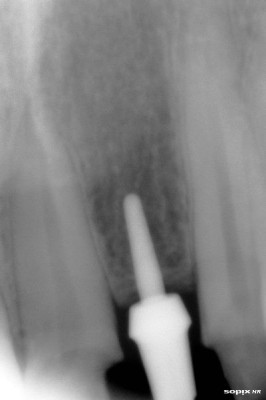

Radiografía inicial

Post Image